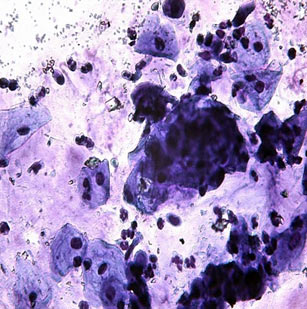

Підсихання та втрата клітин, що прилипли до інструменту, також зменшує діагностичну цінність препарату. Рідинна цитологія дозволяє уникнути всіх цих проблем, а також стандартизувати процедуру відбору та розміщення зразків на склі і отримати якісні моно шарові цитопрепарати. Ця методика є універсальною, але найбільшого поширення вона набула у цервікальній цитології.

Протягом останніх 35 років Shandon Cytospin є синонімом цитоцентрифуги у всьому світі. Понад 15000 лабораторій світу використовують цей прилад для приготування досконалих цитологічних препаратів на основі рідинної цитології. Ця центрифуга необхідна при роботі з гіпоклітинними суспензіями, такими як, цитологічні зразки пухлин, ліквор, сеча.

Цитоцентрифуга Shandon Cytospin 4 дозволяє приготувати оптимальні цитологічні препарати, які містять моношар розпластаних і фіксованих на склі клітин. При цьому клітини не накладаються одна на одну, та не ушкоджуються. Одночасне завантаження до 12 зразків. Спеціальна насадка на ротор має захисну кришку й може використовуватися окремо від центрифуги. Вона також дозволяє зручно завантажувати скельця та зразки, і переносити готові препарати. Прилад створено у відповідності до всіх вимог безпеки. Під час роботи центрифуги її кришка автоматично блокується, і залишається закритою до повної зупинки ротора. Частини приладу, які потенційно можуть бути контаміновані, легко знімаються, очищуються, і створені із матеріалів, які можна знезаражувати шляхом автоклавування. Програмування приладу відбувається за допомогою сенсорної клавіатури. На дисплеї відображається вся інформація про параметри програмування. Центрифуга оснащена пам’яттю на 9 програм. Можливо програмування швидкості у діапазоні 200-2000 об/хв., часу у діапазоні 1-99 хвилин. Після зупинки ротору передбачено звукове повідомлення про завершення роботи, яке допомагає уникнути пересихання препаратів. Аварійна сигналізація повідомить оператора про будь-яку невідповідність у роботі приладу – відсутність балансу, відчинену кришку тощо.